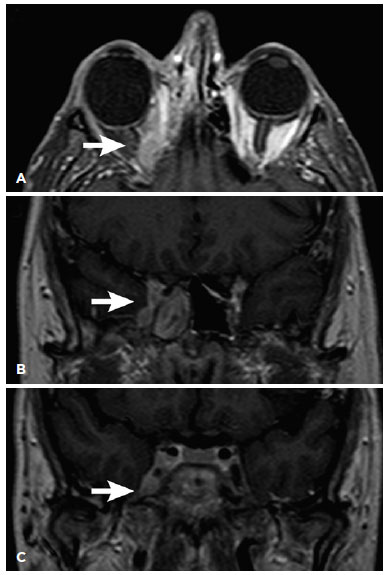

CT scans of the skull and orbits revealed a superior nasal orbital lesion associated with veiling of the maxillary and ethmoid sinuses on the right side. Diagnostic sinusectomy revealed fungal hyphae compatible with mucormycosis, and the patient was started on intravenous amphotericin B deoxycholate. After a month’s time, ophthalmoplegia developed and progression to the cavernous sinus was visible on the orbital MRI (Figure 1). Amphotericin B deoxycholate was replaced with liposomal amphotericin B owing to nephrotoxicity and clinical-radiological progression of the condition. Despite the intravenous treatment and 3 sinusectomies performed by the otorhinolaryngology team, orbital proptosis increased and ophthalmoplegia worsened, which resulted in severe visual impairment. At this point of time, VA was absence of light perception in OD and 20/20 in the left eye, with restricted ocular motility (Figure 2) and an absolute afferent pupillary defect in OD. The only finding on biomicroscopy was conjunctival hyperemia in OD. Intraocular pressure was 12 mmHg in OU, and the optic nerve in OD displayed atrophy on fundoscopy.